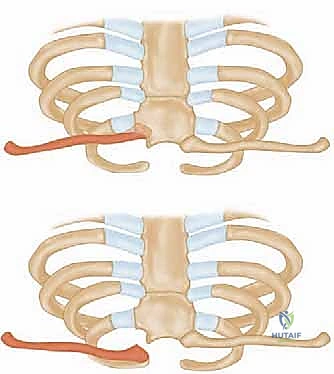

يتكون المفصل من التقاء عظم الترقوة (Clavicle) بعظم القص (Sternum).

* القص والضلع الأول: يتصل السطح المفصلي للترقوة بالشق الترقوي للقص، وفي بعض الأحيان يشمل التمفصل غضروف الضلع الأول. التوافق العظمي هنا ضعيف جداً (أقل من نصف السطح المفصلي للترقوة يلامس القص)، مما يجعل المفصل غير مستقر عظمياً بطبيعته.

بما أن العظام لا توفر الاستقرار، يعتمد المفصل بنسبة 100% على شبكة معقدة وقوية جداً من الأربطة:

- الأربطة الكبسولية (Capsular Ligaments): تغلف المفصل بالكامل. الكبسولة الخلفية هي البطل الحقيقي هنا، فهي أقوى المكونات والمثبت الأساسي الذي يمنع الترقوة من الانزلاق للأمام أو للخلف.

- الرباط بين الترقوتين (Interclavicular Ligament): يمتد بين الترقوتين عبر أعلى القص، ويعمل كجسر توازن يمنع هبوط الكتف.

- القرص المفصلي (Intra-articular Disc): قرص غضروفي ليفي يعمل كممتص للصدمات ويفصل المفصل إلى تجويفين، ويمنع اندفاع الترقوة للداخل نحو الرقبة.

- الرباط الضلعي الترقوي (Costoclavicular Ligament): رباط قوي جداً يربط أسفل الترقوة بالضلع الأول، وهو المثبت الرئيسي الذي يقاوم سحب العضلات للترقوة إلى الأعلى.